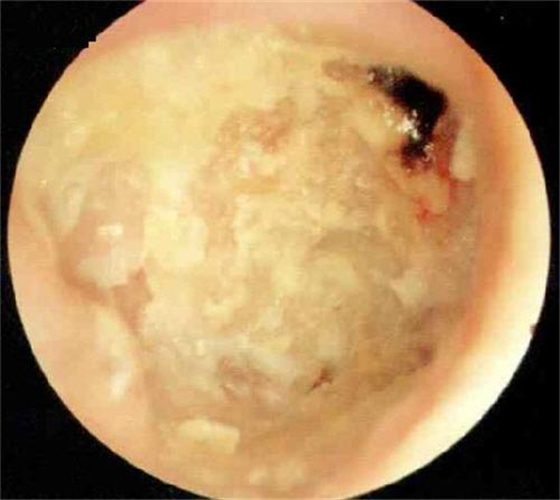

脂肪組織修補鼓膜穿孔